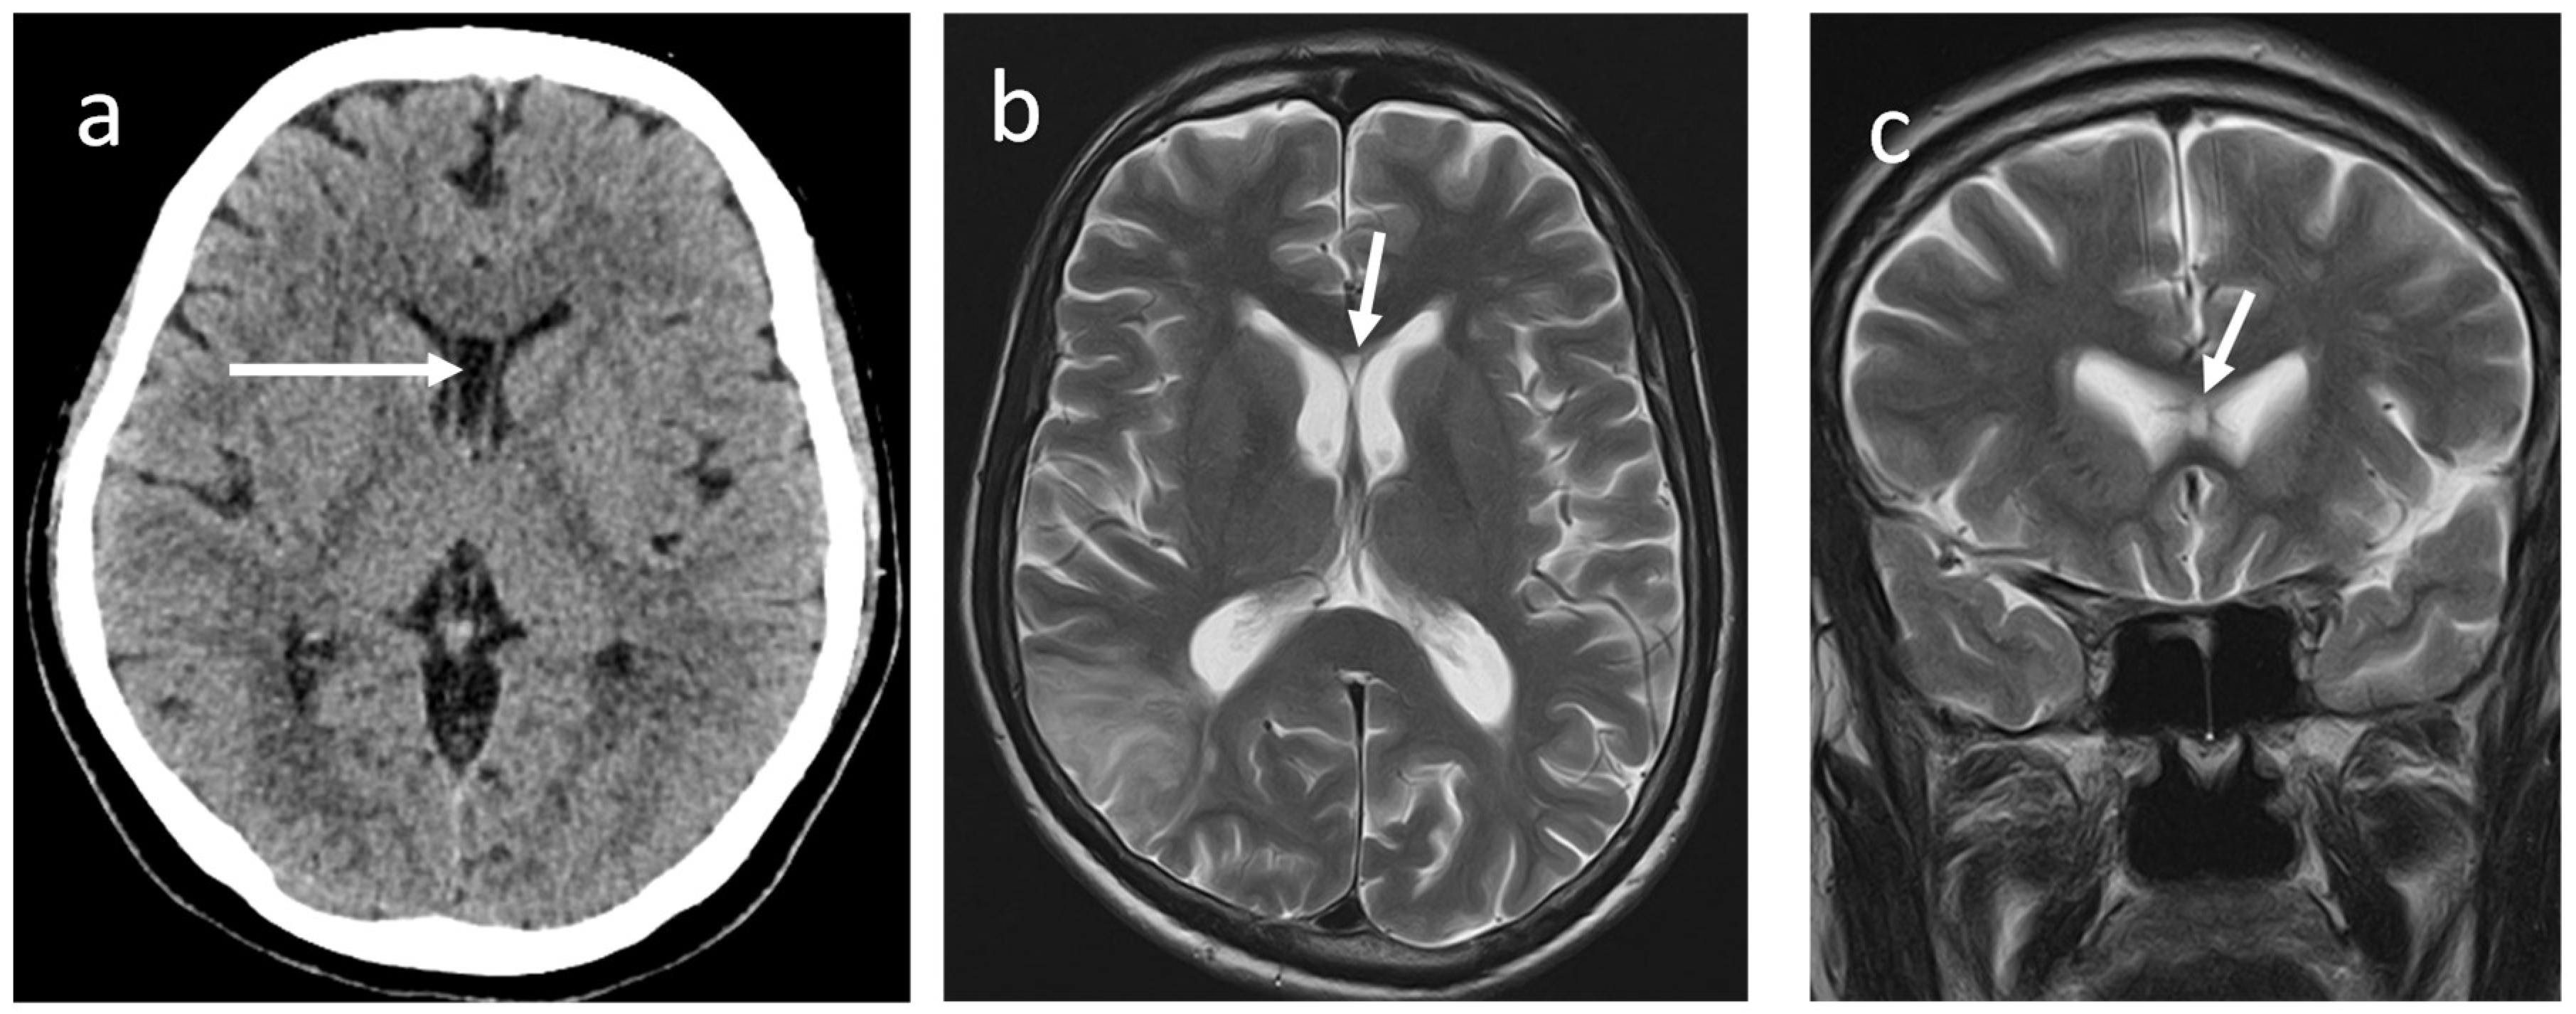

CV has the following boundaries: anteriorly; the anterior limb of the fornix, superiorly; the body of the corpus callosum, posteriorly; the splenium of the corpus callosum, inferiorly; the hippocampal commissure (5).They demonstrated a concurrent prevalence of around 21.1% for CSP and CV in healthy adults using an MRI brain study and isolated CV in 4 % of subjects. Nakano et al. found that the average prevalence of CV alone in 1,050 children was 0.4% using CT brains (8). However, Schwidde et al. did not find CV alone in any of the 1,032 CT brains they examined(9). When associated with CSP, the CV is collectively known as the cavum septum pellucidum et vergae (CSPV) (Figure 4a-c).

The MR/CT findings of the SP and its variations are straightforward and represented by the presence of a fluid-filled cavity between the two leaflets of the SP. Therefore, this will follow CSF signal intensity in all the MRI sequences. This is characterised by low signal intensity on T1W, high signal intensity on T2W and suppression of signal in FLAIR sequences. The rapid advancement of in utero magnetic resonance (iuMR) imaging techniques has increased the prenatal detection of abnormalities in the corpus callosum, such as the absence of the corpus callosum, a narrow or wide corpus callosum, and abnormal shape of the corpus callosum (17).After conducting a study on 200 iuMR in foetuses ranging from 18 to 37 weeks of gestational age, Javis et al. concluded that the CSPV length constantly increased throughout pregnancy. This increase likely implies the rapid expansion of the cerebral hemispheres during the second and third trimesters. On the other hand, the width and volume of the CSPV peaked between 29 and 31 weeks of gestational age and subsequently decreased during the later stages of pregnancy. They further stated that the width of the cavum septi pellucidi is larger than the width of the cavum vergae at each stage of gestation. Born et al. studied three age groups involving 151 healthy subjects. The study revealed that the length of the SP was measured to be 28 ± 6.9 mm in children, 35 ± 7.3 mm in young adults, and 37 ± 5.0 mm in elderly adults (mean ± SD) (18).Tsutsumi et al. applied the Coronal Interference Steady State (CISS) sequence, a gradient-echo MR imaging technique, to precisely delineate a wide range of pathologies. This method proves valuable when standard MR imaging sequences fail to provide adequate anatomical details and enhanced sensitivity in diagnosing conditions such as CSP, CV, and CVI (19).

Figure 4a-c. Non-contrast MRI bran of a 77-year-old male (a) axial T1W, (b) coronal T2W, and (c) sagittal T1W images show CSPV (arrow). Note that a moderate degree of cerebral atrophy is also present.